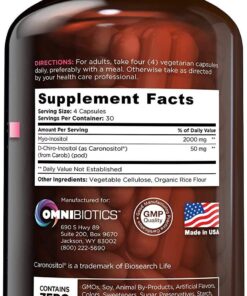

Product Details:

- Brand: OmniBiotics

- Flavor: Unflavored

- Primary Supplement Type: Myo-Inositol

- Unit Count: 120.00 Count

- Item Form: Capsule

- Item Weight: 0.14 Kilograms

- Item Dimensions LxWxH: 4 x 4 x 5 inches

- Special Ingredients: Vegetarian, Gluten Free, Vegan

- Diet Type: Vegetarian, Gluten Free, Vegan

- Product Benefits: Hormone Balance

- Is Discontinued By Manufacturer : No

- Product Dimensions : 4 x 4 x 5 inches; 4.8 Ounces

- Date First Available : October 14, 2016

- Manufacturer : OmniBiotics